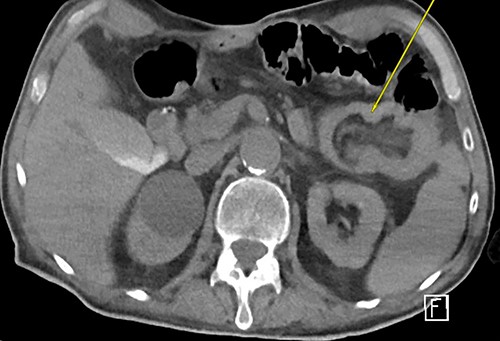

Three weeks later, he presented with a JT obstruction. Multiple attempts using carbonated fluids, enzymes and mechanical brushing failed to clear the obstruction. A computerized tomography of the abdomen and pelvis (CTAP) confirmed the position of the JT and demonstrated telescoping of a long 17 cm segment of jejunum starting from the tip of the JT as lead point (Fig. 1). The JT was removed in hopes of resolution. However, repeat CTAP showed persistent intussusception with mesenteric fat stranding, and possible intestinal ischemia (Fig. 2).

CT abdomen and pelvis revealing telescoping of J-tube (yellow arrow).